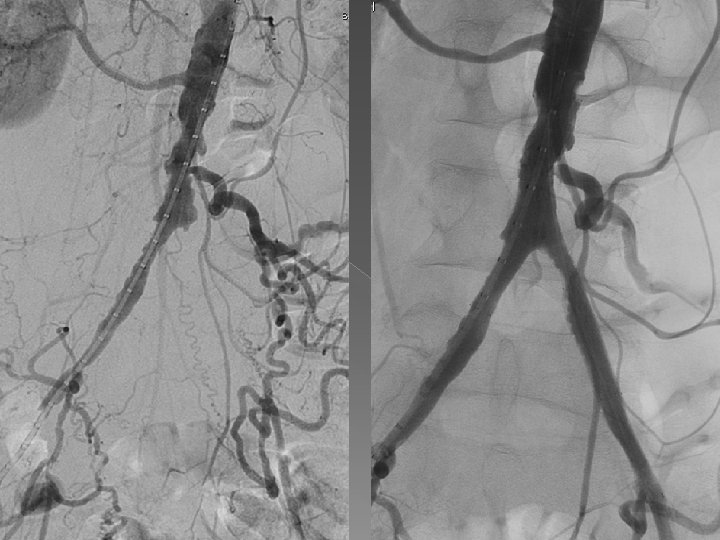

TANI (vaskülojenik impotans) � Fizik muayene-laboratuvar testler, erektil disfonksiyon testleri (IIEF, SHIM) � İlk tanısal yöntem: intrakavernozal enjeksiyon (papaverin-fentolamin) eşliğinde renkli Doppler US � Altın standart: pelvik DSA � Kavernoskopi � Kavernozografi-kavernozometri � Penil-brakial indeks

ENDOVASKÜLER TEDAVİ � Oral medikal tedaviye yanıt yoksa � Cerrahi tedavi düşünülmüyor ve penil

ENDOVASKÜLER TEDAVİ � Oral medikal tedaviye yanıt yoksa � Cerrahi tedavi düşünülmüyor ve penil protez öncesi minimal invaziv (endovasküler) tedaviye şans vermek � Arteryel hastalıkta: rekanalizasyon/PTA/Stentleme/ilaç kaplı stent (2009 ZEN çalışması, 2012 LINC sunumu) � Veno-oklüziv hastalık: embolizasyon (antegradperkütan/retrograd-transfemoral)